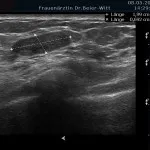

Mammasonographie:

Ultraschall_24